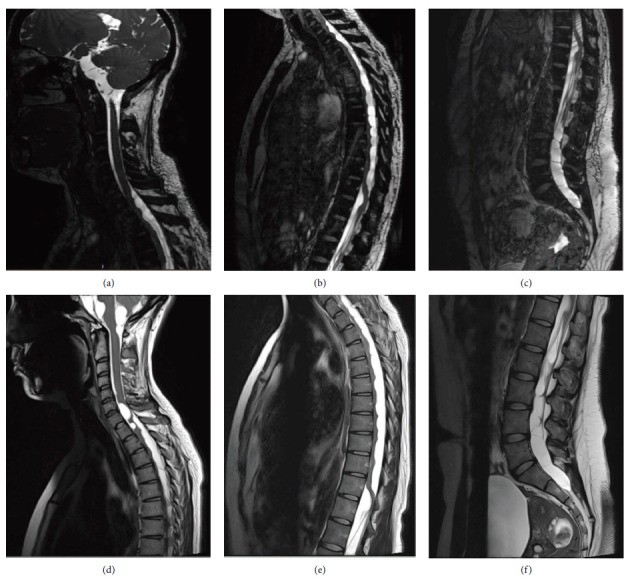

Neurenteric cysts (NECs) are rare congenital, benign lesions of the central nervous system (CNS), predominantly located within the spinal cord. However, they may also occur less frequently within the brainstem, fourth ventricle, or cerebellopontine angle (CPA). Originating from anomalous interactions between embryonic layers, NECs are recognized for their potential to compress adjacent structures. We report a unique case of disseminated NECs exhibiting few to absent symptoms, which represents an unusual presentation of this disease, with only six similar reports in the literature. A 22-year-old female presented to our institute with chronic headaches resistant to nonsteroidal anti-inflammatory drugs (NSAIDs). Initially treated for intracranial hypertension (ICH) secondary to a cyst in the quadrigeminal cistern at the age of 17 via neuroendoscopic surgery and subsequent ventriculoperitoneal shunting, she experienced transient relief. However, follow-up at 22 years of age revealed multiple cysts in the basal and spinal cisterns, with MRI findings suggestive of neurocysticercosis. Despite treatment with albendazole and corticosteroids, subsequent MRIs showed no change in the size or number of the cysts. Six years later, symptoms had worsened, previously identified cysts had grown, and the detection of new cysts prompted surgical intervention. Histopathological examination confirmed the presence of NECs. This case highlights the diagnostic challenges posed by NECs, especially in regions endemic for neurocysticercosis, where clinical and radiological findings may initially suggest this condition. It underscores the importance of considering NECs in the differential diagnosis of cystic lesions in the CNS, even in the absence of typical symptoms of spinal cord compression. The recurrence and spread of NECs post-treatment demand a comprehensive management approach, encompassing surgical intervention and close monitoring.